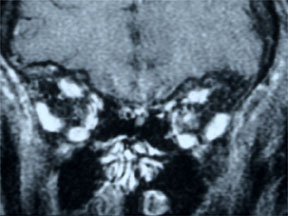

MRI结果

|

- 左眼视神经增强伴颅内蔓延,病损累及第二视神经 (图 3, 4 ,5)

- 符合视神经脑膜瘤的表现

- 肿瘤可能起源于眶内的视神经鞘膜在颅内孔处,向颅内生长